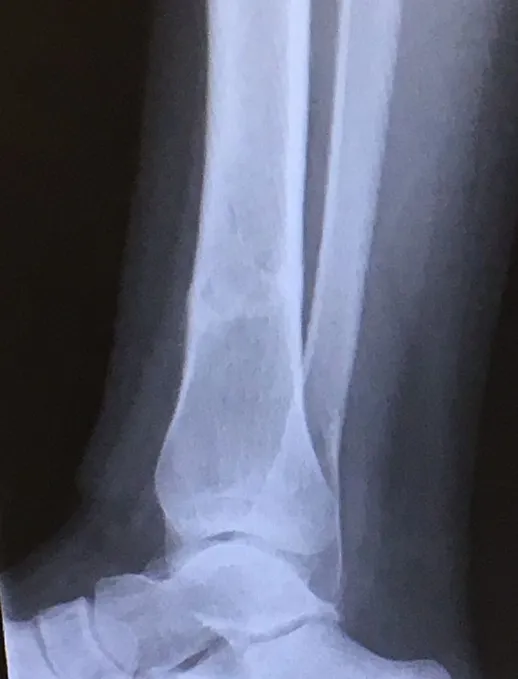

Below, Tibia and Fibula Fracture in a 16-year-old injured skiing. The patient presented to the office 8 days after injury with a displaced fracture. The first 2 films show the displacement in the fracture of the tibia. After an above knee cast is applied, the cast is wedged under fluoroscopy and new xrays show the near perfect reduction of the fracture. The white arrows show the area where the cast is wedged

Xray of Tibia Fracture